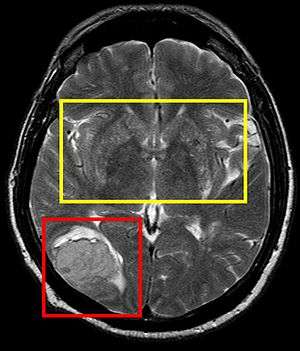

In medicine, cerebral softening (encephalomalacia) is a localized softening of the brain substance, due to hemorrhage or inflammation. Three varieties, distinguished by their color and representing different stages of the morbid process, are known respectively as red, yellow, and white softening.[1][2]